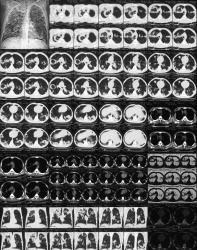

Больной поступил после двухнедельного лечения в районном стационаре - температурные свечки до 39, ускоернное СОЭ. Но данные рентген-исследований заставили направить больного в область, к нам. Снимочки шокировали:

Исследование на МБТ, так как картина напоминает казеозную пневмонию. На рентгенограмме от 19.05.09. субплеврально свободный газ - пневмоторакс.

... мне кажется - при таких объемах казеозный распад неизбежен - посмотрите КТ - полиморфные шаровидные образования, а вместо распада внутри - легочная ткань! Смотрели и сеяли трижды в районе и трижды у нас при поступлении - "-".

Первое мое заключение (ночью в приемном покое) гласило: септическая пневмония (откровенно пошел на поводу у клинициста с её картиной сепсиса в анамнезе) / множественные метастазы с распадом.

Потом сделали контроль - посмотрите - динамики за 2 недели при массивной антибиотикотерапии 0. Что за "Septic pneumonia" без динамики? А по данным КТ распада нет! Даже в самом мелком "шарике" серединка из легочной паренхимы! Сейчас ничего (кроме нашего пневмоторакса) не беспокоит. Только СОЭ 51.

По поводу гематогенных MTS: на первый взгляд похоже(четко очерченные, округлые очаги с ровными контурами, некоторые из которых имеют четкую связь с сосудами).

Однако посмотрите, то что нам видеться как кольцевидные тени(на рентгенограммах), это скорее всего: внутри участок легочной ткани после разрешившейся пневмонической инфильтации, а"кольцо" вокруг, еще консолидированная легочная ткань( посмотрите на КТ сканы - там (в уплотненной легочной ткани, которая в виде"кольца")хорошо видны просветы бронхов" с-м воздушной бронхографии", и в нижних отлелах - определяются множественные участки уплотнения легочной ткани с тенденцией к слиянию и наличием вышеописанного с-ма. Поэтому может я и ошибаюсь, но действительно похоже на пневмоническую инфильтрацию с дисс.

Но, смущает наличие атипичных клеток. А что если здесь два параллельных процесса? На фоне MTS + пневмоническая инфильтрация?

КТ-картина складывается из мозаично расположенных фокусов уплотнения легочной ткани по типу матового стекла и по типу альвеолярной консолидации, расположенных преимущественно в периферических отделах. При разрешении процесса на месте уплотнения образуется сетчатый фиброз. Характерно распространение процесса от центра фокуса к его периферии, что создает характерную картину атолла: по краям зоны поражения - "свежий" инфильративный процесс, а в центре - уже воздушная, но фиброзно измененная легочая ткань.

Вот. По-ммоему ничего не изменилось...

По-моему сканер глючит - левая половина темнее получилась, чем в оригинале. Попытался "вытянуть":

... кое какая (количественная, но, по-моему не качественная) динамика всё же есть, тем более, что я не выложил (каюсь!) промежуточный снимок. После ликвидации пневмоторакса тени "легли" несколько по-другому. Я позже выложу.

С точки зрения врача-рентгенолога с "глубокой периферии" в настоящее время классическая картина метастазов.

Не возникала, она, по всей видимости, потому, что вокруг метастазов был "парапроцесс", возможно банальная пневмония, которая весьма часто имеет место быть, рядом с опухолевым узлом (узлами). А потом все это завуалировалось еще частичным спадением правого лёгкого - пневмоторакс.

В настоящее время, с учетом массивной противовоспалительной терапии "парапроцесс" ушел, и мы имеем картину "типичных метастазов" в органов грудной полости. Но это лично моя точка зрения - точка зрения рентгенолога "с глубокой периферии".

Кстати, весьма интересный задний фрагмент 7 ребра справа. Этого раньше не было.